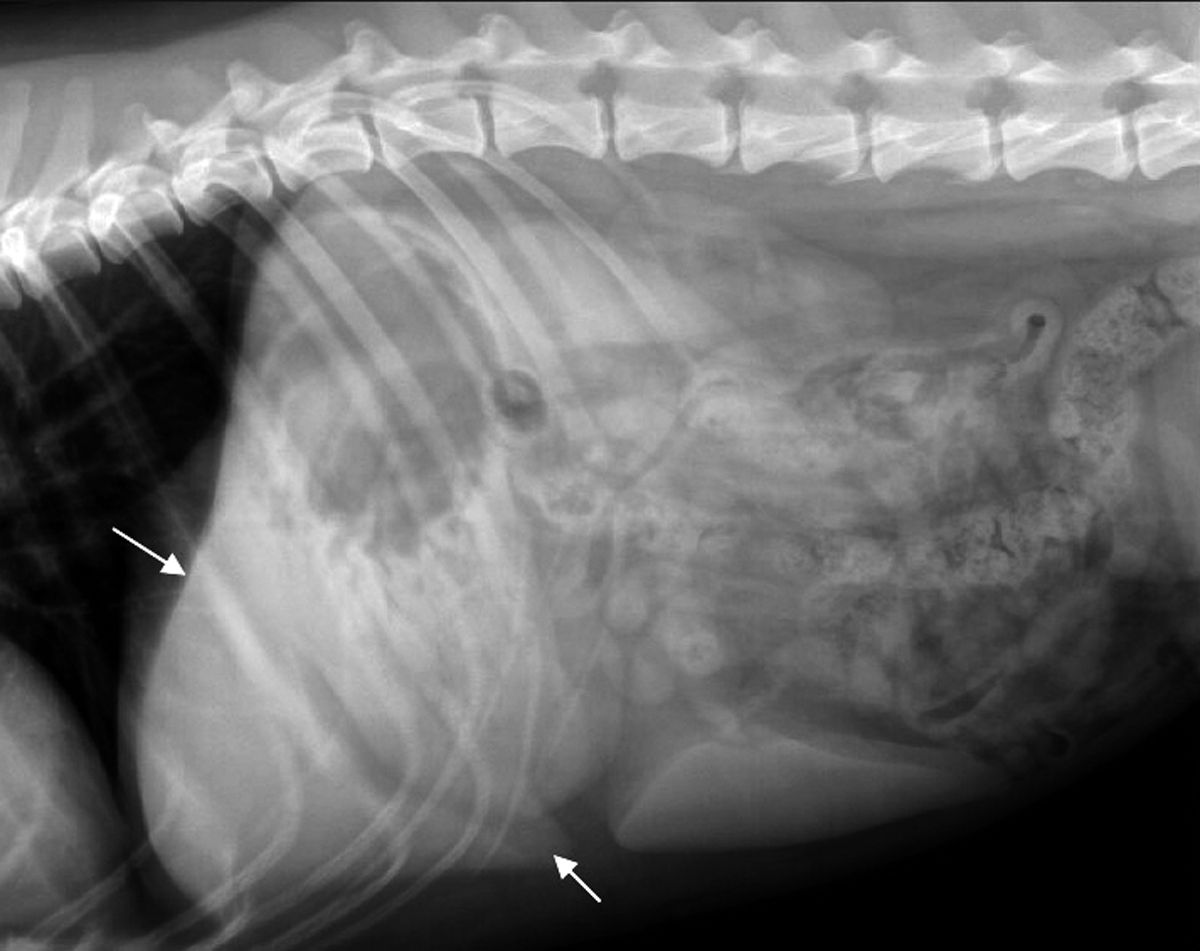

La silhouette epatica non può essere differenziata dal diaframma e viene delineata caudalmente dallo stomaco. L'aspetto caudoventrale del fegato normale ha margini netti (Figura 1a) (Figura 1b). L'asse gastrico può aiutare a valutare le dimensioni del fegato, dal momento che dovrebbe essere visibile in proiezione laterale nell'area compresa tra la linea tracciata a 90 gradi rispetto alla colonna vertebrale e quella parallela all'ultimo paio di coste. Si parla di epatomegalia quando l'asse gastrico è dislocato oltre l'ultimo paio di coste, o il margine caudoventrale del fegato si estende caudalmente alla faccia ventrale dello stomaco. Se lo stomaco è dislocato cranialmente, allora il fegato è probabilmente piccolo, anche se questo aspetto può essere normale nei cani a torace profondo (Boxer, Dobermann o Alano). Le epatopatie sono spesso associate ad ascite, che può precludere la valutazione del fegato, ma la presenza di fluido peritoneale, caratterizzato dalla perdita di definizione di sierosa e, nei casi gravi, dalla presenza di addome pendulo, è generalmente facile da riconoscere nelle radiografie addominali.

Radiografia addominale di un cane (proiezione ventrodorsale) che mostrano un fegato normale (frecce bianche). Il margine caudoventrale del fegato normale ha aspetto angolato.

Figura 1a. Radiografia addominale di un cane (proiezione ventrodorsale) che mostrano un fegato normale (frecce bianche). Il margine caudoventrale del fegato normale ha aspetto angolato.© Laurent Blond

Radiografia addominale di un cane (proiezione laterale) che mostrano un fegato normale (frecce bianche). Il margine caudoventrale del fegato normale ha aspetto angolato.

Figura 1b. Radiografia addominale di un cane (proiezione laterale) che mostrano un fegato normale (frecce bianche). Il margine caudoventrale del fegato normale ha aspetto angolato.© Laurent Blond